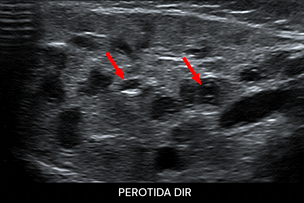

Texto alternativo para a imagem Figura 1. Créditos: Dra. Elazir Mota - Rio de Janeiro/RJ

Descrição da figura 1: Ultrassonografia da região cervical evidenciando a glândula parótida direita aumentada de volume e heterogênea, com ectasia dos ductos glandulares (setas vermelhas).

• U ltrassonografia cervical: E xame de imagem de escolha na população pediátrica. Demonstra com clareza o aumento de volume da glândula, sua heterogenicidade, com focos hiperecogênicos puntiformes que representam a ectasia dos ductos glandulares e linfonodos de permeio, bem como aumento da vascularização no estudo com Doppler colorido (f igura 1) ;